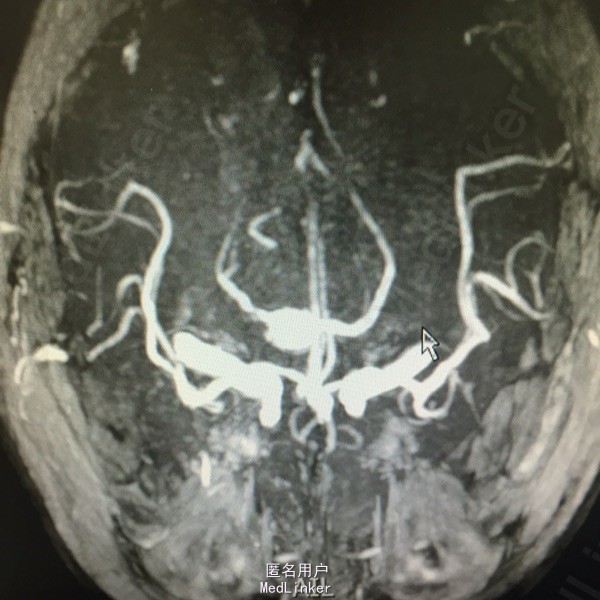

头痛伴视物双影5天。既往高血压、糖尿病、脑梗死。该患于入院前5日无明显诱因出现视物双影,偶伴头痛,不伴有恶心、呕吐,无视物旋转,无吞咽困难,病程中无肢体活动障碍,无言语不清,无意识障碍及尿便失禁。曾有中耳炎病史,伴有听力减退,曾于入院前3日在眼科医院激光治疗眼底出血。为求进一步诊治而来我院。

查体:神清语利,左眼内收受限,鼻唇沟对称,伸舌居中,双耳听力减退,肌力肌张力正常,双下肢病理症(-)颈强(-)。

诊断:脑梗死、高血压、2型糖尿病、高脂血症、中耳炎 治疗:营养神经、改善循环、神经生长因子、降脂、抗炎对症治疗。